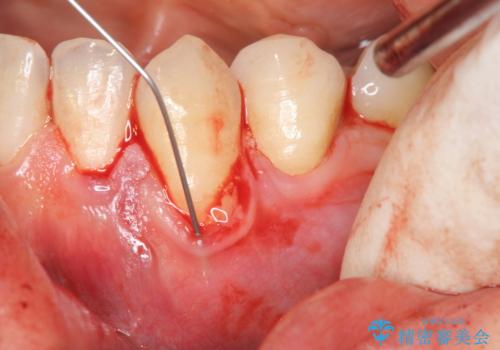

- 下の犬歯の歯茎の下がりを気にされていました。

矯正治療予定であったので、矯正治療前に歯茎の移植を行い、さらに退縮するのを防ぎました。

下がったのを元に戻すことは必ずしもできないですが、厚みを増やして下がりにくくすることはできます。今回左下の犬歯は特に、しっかり下がったのも元に戻すことができ、大変うまくいきました。